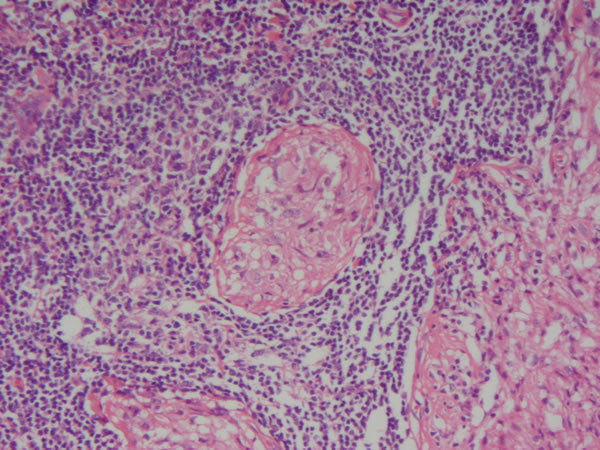

| Rim - Parênquima cortical ( tem glomérulo) Degeneração hialina - Amiloidose (deposição de material eosinofílico amorfo) Causas: metabolismo anormal, defeito no dobramento/transp. proteínas, ingesta de materiais indigeríveis | |

Rim - Parênquima cortical Degeneração hialina - Amiloidose Causas: metabolismo anormal, defeito no dobramento/transp. proteínas, ingesta de materiais indigeríveis |